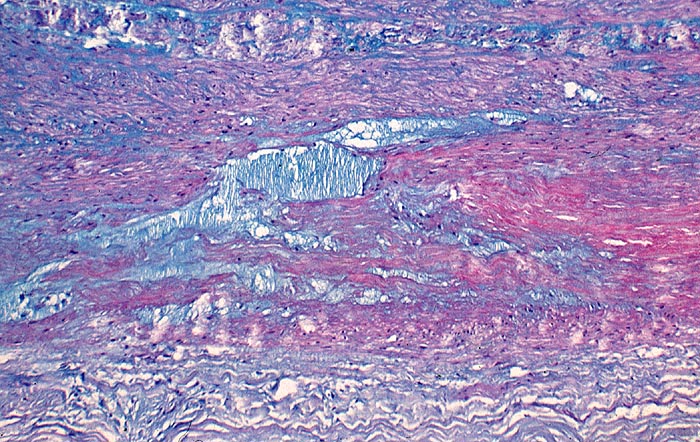

AP/ Zystische Mediadegeneration (Medianekrose)

Zystische Mediadegeneration (Medianekrose)

Kardiovaskuläres System

Aorta

Morphologie